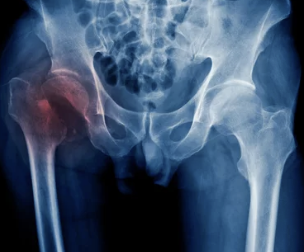

대퇴골두 무혈성 괴사

대퇴골두 무혈성 괴사는 대퇴골두에 혈액 공급이 차단되어 뼈 조직이 죽는 질환입니다. 괴사된 뼈는 점차 무너져 내리고, 이로 인해 고관절 통증이 발생합니다.

원인

- 음주: 과도한 음주는 대퇴골두에 혈액 공급을 방해할 수 있습니다.

- 부신피질 호르몬: 부신피질 호르몬 치료는 대퇴골두 무혈성 괴사의 위험을 증가시킬 수 있습니다.

- 고관절 부위 외상: 사고나 부상으로 인해 대퇴골두에 혈액 공급이 차단될 수 있습니다.

- 기타: 잠수병, 통풍, 혈청지질 이상, 만성 신질환, 만성 췌장염 등